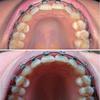

Дуга самая тонкая из прямоугольных. Я думала, что широкий край будет вперед смотреть, оказалось вверх. Когда прямо смотришь, не сильно заметно, что дуга потолще. Как я и предполагала, зубки повернулись по оси. Уже почти с двух месяцев вид ВЧ снизу не менялся, а тут за месяц такой прогресс! Ясно, не идеал, так и время еще есть. Я уже настроилась на 2 года, даже обратный отсчет поставила в профиле, хотя срок снятия не оговаривали с

врачом, рано еще.

Ну, и собственно прогресс:

Нв НЧ тоже хорошо по дуге выстроились за месяц, хотя тоже не идеально. Пока не могу поймать нужный ракурс. Зато по высоте все пляшут, надеюсь, на более толстых дугах и это исправится.

Что-то получилось с фото НЧ: